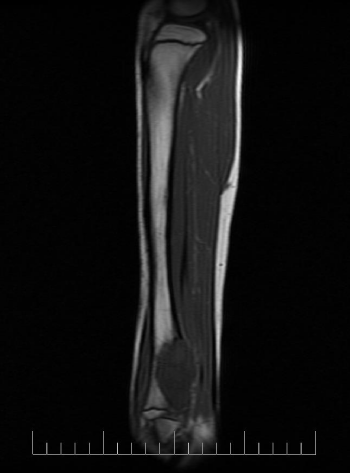

A 10-year-old female presented with left lower leg pain that had progressively increased over the duration of 1 year. On physical examination, tenderness was elicited on palpation of the distal tibia. Routine laboratory testing was normal. X-Ray was performed and revealed a lytic lesion with sclerotic margins in the left lower tibia (Figure 1). MRI was subsequently performed, demonstrating a left lower tibia lesion with low signal intensity on T1 weighted images (Figure 2), and high signal intensity on T2 weighted images (Figure 3). Pathology of the tumor revealed a diagnosis of a CMF. She was treated with curettage and autologous bone grafting (Figure 4). Post op eratively the left leg was immobilized with a plaster cast with restricted weight bearing (Figure 5). Follow up X-ray after 5 years demonstrates no tumor reoccurrence (Figure 6, Figure 7).

MRI demonstrates low signal intensity on T1 weighted images (Figure 2, Figure 11 and Figure 12). T2 weighted images demonstrate high signal intensity (Figure 3, Figure 13). Post gadolinium contrast T1 weighted sagittal view demonstrates diffuse heterogenous enhancement (Figure 14). Post gadolinium contrast T1 weighted axial view demonstrates peripheral nodular enhancement (Figure 15).

Figure 11: MRI axial T1 of the left tibia